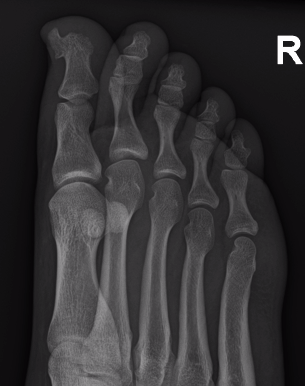

X-ray

Well defined bony mass arising from the surface of the bone

- no medulla